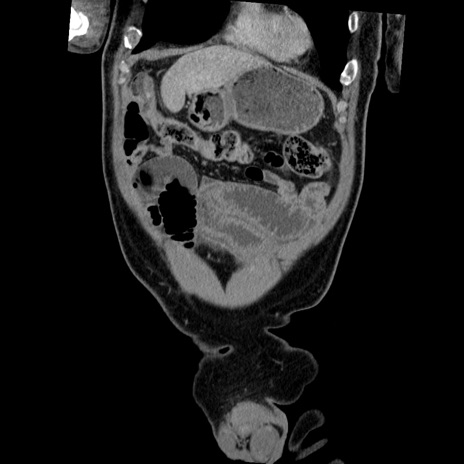

症例22(冠状断像)

【症例】50歳代男性

【主訴】腹痛

【現病歴】AVMからの被殻出血のため回復期リハ病棟入院中。 本日午後3時頃急に下腹部痛が出現した。

【既往歴】AVM、被殻出血、虫垂炎、高血圧

【身体所見】意識晴明、左半身不全麻痺、会話の理解は良好、36.5°C、腹部:膨隆、全体に板状硬、下腹部正中に圧痛点あり、反跳痛-、筋性防御不明、右下腹部にope scar

【データ】WBC 9400、CRP 0.06